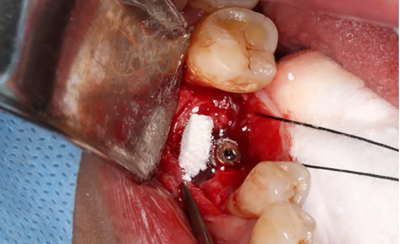

6、牙槽嵴保存術(shù)過程:拔牙及位點(diǎn)保存

(攝于2016年8月31日)

使用直徑3mm的環(huán)形取骨鉆切取長約9mm的柱狀骨標(biāo)本,用于組織學(xué)和顯微影像檢查

(攝于2017年4月14日)

由于取骨致窩洞較大,加之缺牙間隙大,只好選擇植入5mm直徑種植體;種植備洞完成后,頰側(cè)骨壁厚度僅約1mm。

植入國產(chǎn)威高(WEGO)5.0×11mm種植體,檢查種植體位于理想軸位。